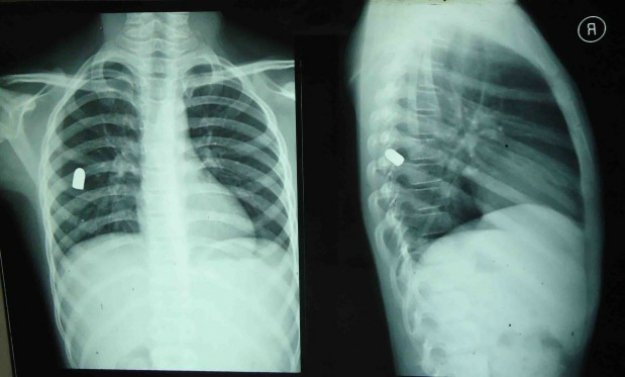

同样,如果*弹子**击中人体躯干,比如胸腹部这些部位,这个绝对就是要命的了,特别是被*弹子**击中后*弹子**没有穿透,而是停留在人体内部,这种情况下就看这个被击中者的运气了,比如*弹子**击中脏器,但是没有直接切断脏器内部血管,比如肺部中弹,但是仅仅击穿肺叶,而没有击穿里面的血管,胃部中弹,肠道中弹等,但是这里并不是说这些伤没事,这些伤是重伤,而且是很危险的,受创的器官会因为失血等失去应有功能导致其他脏器失效,直接导致人体死亡。